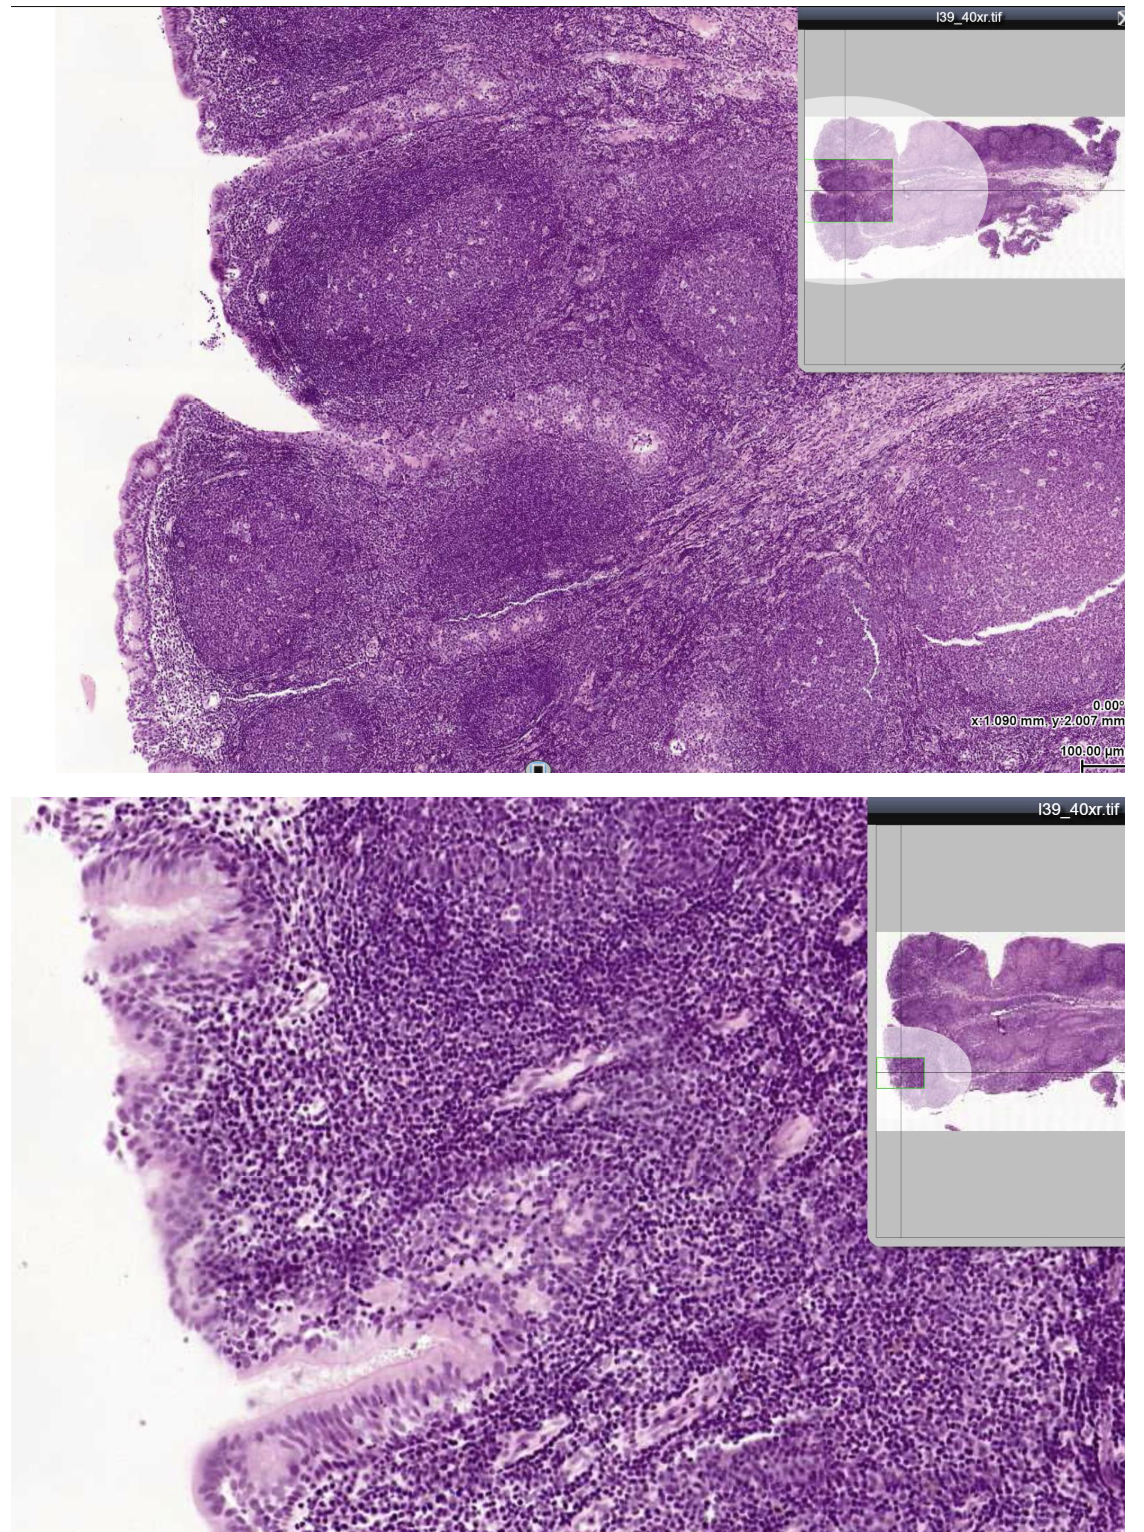

The tissue shown in the linked image is best described by which of the following?

It shrinks after childhood